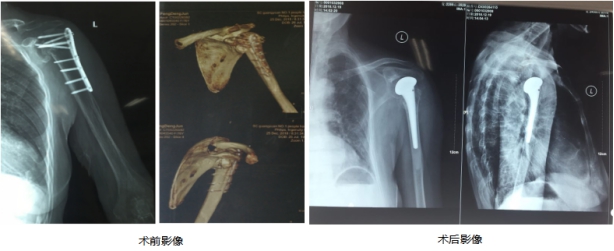

2018年12月29日,市第一人民医院骨一科成功为患者实施左侧肩关节置换手术,成为我市第一家能独立开展肩关节置换手术的医院。

今年76岁高龄的冯奶奶,4年前因外伤导致左侧肱骨近端骨折,当地医院手术后骨折愈合效果差,随后多年左侧肩关节无法正常活动且伴有明显疼痛。近4年来因肩关节问题,冯奶奶生活苦不堪言,先后辗转多家医院骨科就诊,均未获得有效治疗。

2018年12月23日,冯奶奶怀着忐忑的心情来到市第一人医院问诊,检查后经骨一科全体医生认真讨论研究,决定对冯奶奶实施左侧肩关节置换手术。在手术过程中,麻醉科为了更好地配合手术,结合患者病情实施麻醉,既要保证术中患者血压稳定,又要减少药物用量,降低应激反应发生率,保证了患者术中安全,在多科医务人员共同配合下,12月29日,顺利为冯奶奶实施了手术。

骨科黄小俊副主任医师介绍,肱骨骨折是老年人肩部的常见创伤。肩关节置换手术具有术后并发症发生率低,能最大限度保留了肩关节原有功能等优势,是治疗老年肱骨骨折的有效方法之一。该手术适应症还包括骨性关节炎、类风湿关节炎、创伤性关节炎、严重肩袖损伤等。

人工肩关节置换手术是市第一人民医院骨科继开展髋膝关节置换术后又一项新开展的关节置换项目。此例手术的成功开展,为肩关节病患又提供了一种有效的治疗方法,标志着医院人工关节置换水平迈上了新台阶。